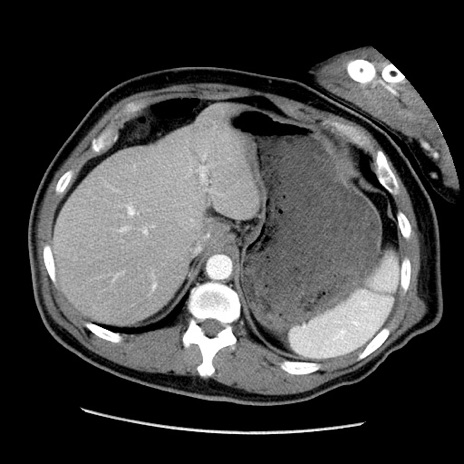

症例22(横断像)

【症例】50歳代男性

【主訴】腹痛

【現病歴】AVMからの被殻出血のため回復期リハ病棟入院中。 本日午後3時頃急に下腹部痛が出現した。

【既往歴】AVM、被殻出血、虫垂炎、高血圧

【身体所見】意識晴明、左半身不全麻痺、会話の理解は良好、36.5°C、腹部:膨隆、全体に板状硬、下腹部正中に圧痛点あり、反跳痛-、筋性防御不明、右下腹部にope scar

【データ】WBC 9400、CRP 0.06